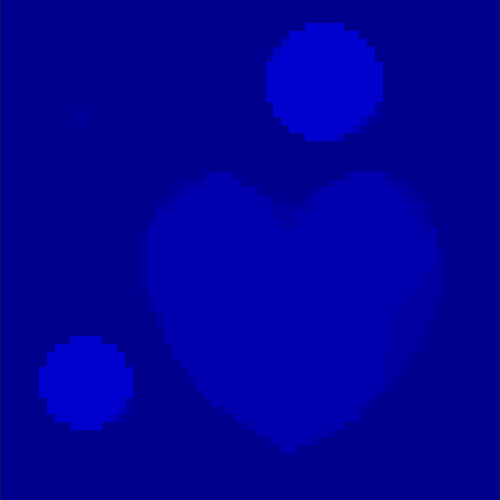

The first data set consists of a heart-shaped region and three circles on a static background (see figure 1 (a)). The two smaller circles are assumed to belong to

the same tissue type and therefore to the same subregion, which causes a total of four subregions, including the background. To simulate a more realistic application of dynamic SPECT

imaging, we used a synthesized representation of a rat liver as a second data set (see figure 1 (b)). The temporal concentration curves used to simulate the data sets

are shown in figure 2. As before, the total number of subregions was chosen to be equal to four in order to provide a both simple and realistic shape model.